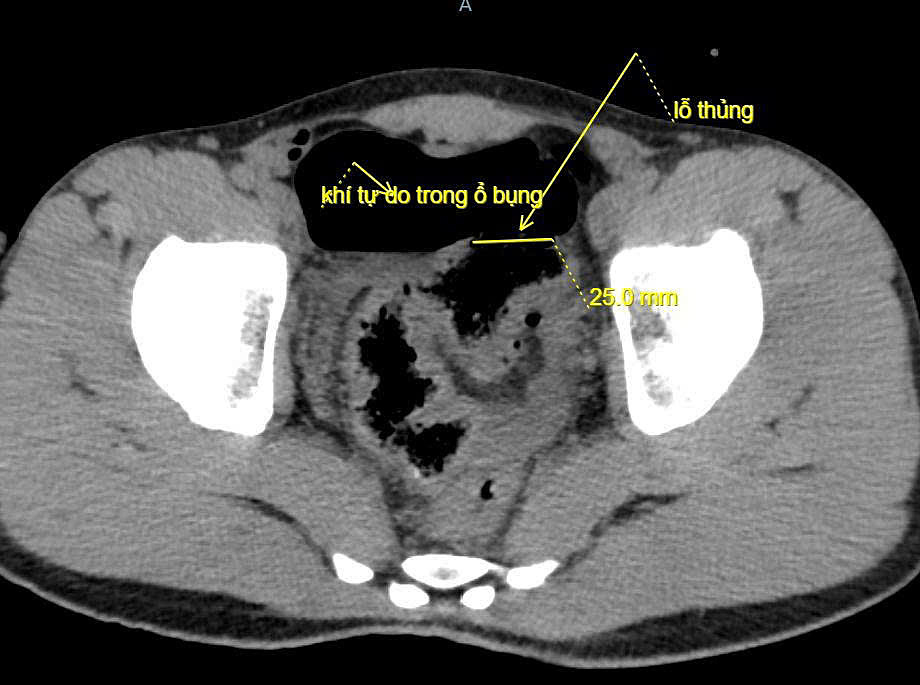

Ngày 20/10, đại diện Bệnh viện Đa khoa Lạng Sơn cho biết bệnh nhân đau bụng dữ dội, bụng chướng căng, khó thở và mệt lả. Kết quả chụp X-quang và CT thấy nhiều khí tự do trong ổ bụng bệnh nhân, bác sĩ nghi ngờ thủng tạng rỗng, chỉ định mổ cấp cứu.

Ảnh chụp CT ghi nhận đại tràng của bệnh nhân bị thủng. Ảnh: Bệnh viện cung cấp

Quá trình mổ, các bác sĩ ghi nhận khoảng 100 ml máu và dịch bẩn trong bụng bệnh nhân, đại tràng sigma có đoạn tổn thương dài 5 cm, thủng khoảng 2 cm và xung quanh dập nát. Bệnh nhân được cắt lọc lỗ thủng, khâu đoạn đại tràng tổn thương, làm sạch ổ bụng và đặt dẫn lưu.